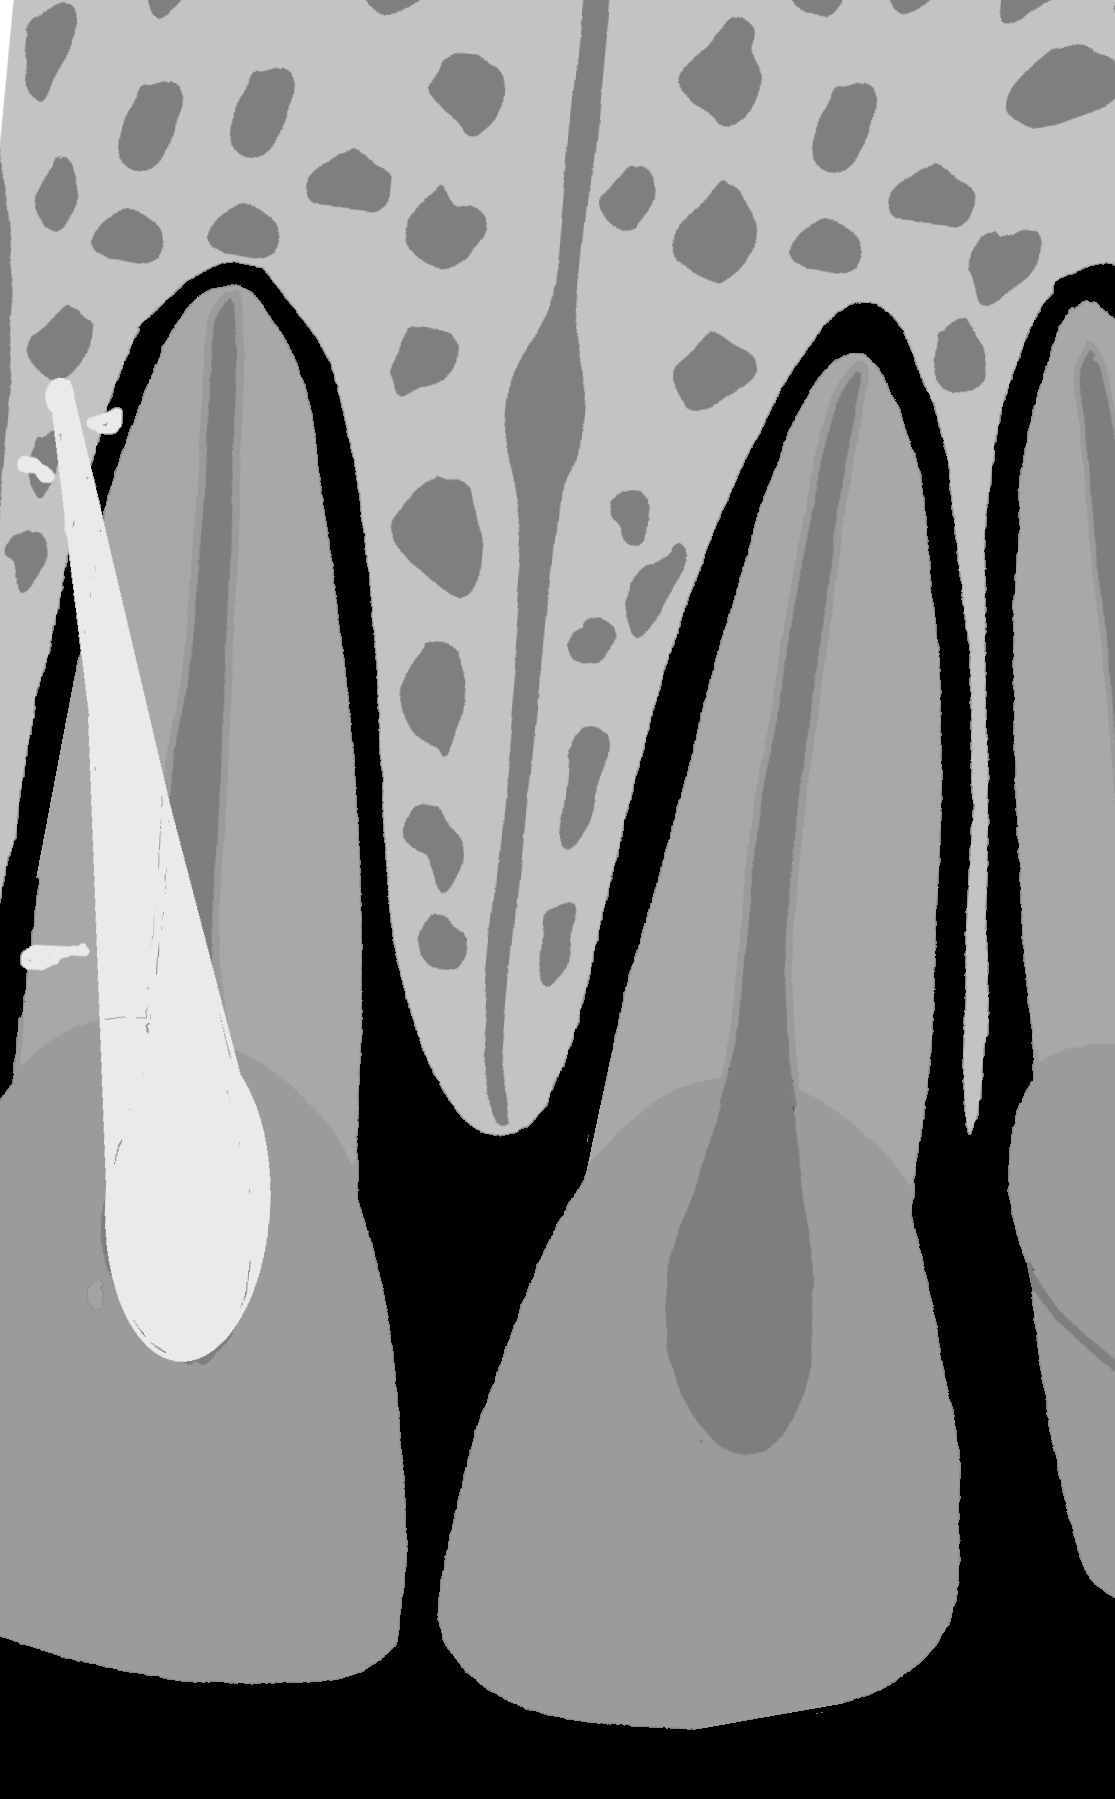

Na kontrolnym zdjęciu rentgenowskiemu wykonanym po wypełnieniu kanału nie rozpoznał perforacji, choć należy przyznać, iż było to dość trudne. Wynikało z faktu, iż operator wypreparował sztuczny kanał w osi właściwego kanału korzeniowego i w związku z tym po jego wypełnieniu obraz materiału umieszczony w kanale perforacyjnym nałożył się na obraz kanału naturalnego (ryc. 1A). Oczywiście doświadczony diagnosta prawdopodobnie zauważyłby niewielkie ilości uszczelniacza poza zarysem kanału i w celu pogłębienia diagnostyki wykonałby zdjęcie rentgenowskie w projekcji skośnej (ryc. 1B), która uwidoczniłaby perforację, lub zdecydowałby się na wykonanie badania CBCT, które wnosi zdecydowanie więcej informacji niż zdjęcie zębowe (ryc. 2A, B). Taką decyzję podjął zresztą endodonta, który wykonał CBCT. Badanie wykazało wypełniony materiałem sztuczny kanał perforacyjny położny dowargowo od nietkniętego kanału naturalnego. Ponieważ wynik badania wrażliwości miazgi prądem faradycznym nie różnił się od zębów sąsiednich, endodonta poinformował pacjenta, że ponowne leczenie może ograniczyć się wyłącznie do usunięcia gutaperki i zamknięcia perforacji. Ostatecznie jednak nie udało się uniknąć leczenia endodontycznego, a ze względu na trudności usunięcia gutaperki od strony jamy zęba wykonano zabieg chirurgiczny i usunięto ją od zewnątrz.

Ryc. 2. Możliwości diagnostyczne CBCT. Badanie rozwiewa wszelkie wątpliwości co do powikłania w postaci perforacji korzenia. A. Skan strzałkowy. B. Skan poprzeczny wykonany dowierzchołkowo od miejsca perforacji. Żółtą strzałką zaznaczono ćwiek gutaperkowy.